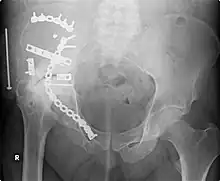

External fixation of fractures was refined by American surgeons during the Vietnam War, but a major contribution was made by Gavril Abramovich Ilizarov in the USSR. He was sent, without much orthopedic training, to look after injured Russian soldiers in Siberia in the 1950s. With no equipment, he was confronted with crippling conditions of unhealed, infected, and misaligned fractures. With the help of the local bicycle shop, he devised ring external fixators tensioned like the spokes of a bicycle. With this equipment, he achieved healing, realignment, and lengthening to a degree unheard of elsewhere. His Ilizarov apparatus is still used today as one of the distraction osteogenesis methods.[12]